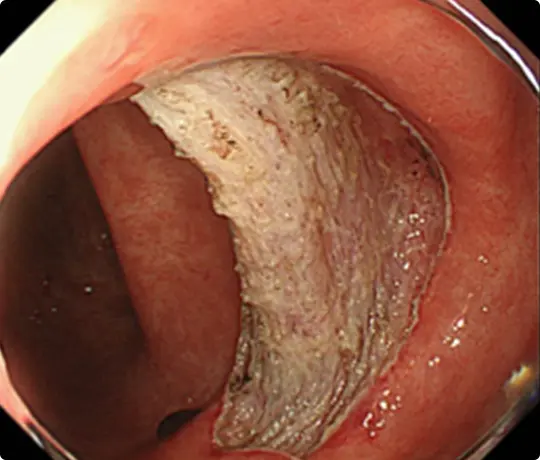

約25mmの十二指腸腫瘍を認めます。

穿孔(壁に穴があくこと)などの問題なく、病変を切除しました。

切除後は潰瘍が出来ますが、1~2ヵ月で治ります。十二指腸ESD後は、遅発性穿孔予防のため、クリップなどで治療後の潰瘍を完全に閉じるようにしています。

切除した検体をピンで伸ばして、ホルマリンで固定後、病理診断を行います。中央に見える赤く隆起している部分が腫瘍です(青い色素をかけています)。

病理診断で腫瘍は完全に切除されており、治癒と判定されました。